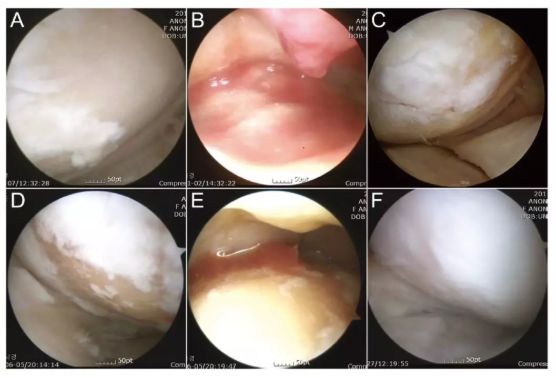

關節鏡下評價 ADSC 移植治療膝骨關節炎軟骨損傷

(Am J Sports Med, 2014)

參與者人數:N=35

治療方案:將 3.8*10^6 脂肪間充質干細胞注射到關節腔內,并在治療后約 24-36 個月測試結果。

評估指標:IKDC 評分丨關節鏡檢查丨主訴

研究結果:ADSCs 治療可以顯著改善膝骨關節炎,BMI 越高效果越差。

注:上圖中 A-C 為 51 歲男性膝關節鏡,D-F 為 54 歲女性膝關節鏡。A/D 為治療前,白色示意軟骨,淺黃色示意裸露的骨。B/E 為間充質干細胞注射。C/F 為治療后的關節鏡檢查。